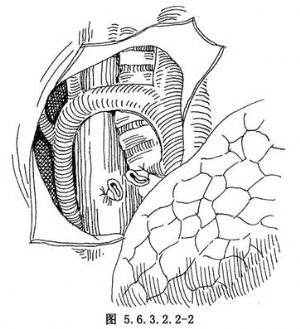

食管中段牵引型憩室的手术治疗方法有:憩室切除术、憩室翻入埋缝术、食管支气管瘘缝扎修补术以及食管部分切除食管胃吻合术等。憩室并发癌变或不能逆转的瘢痕狭窄,应行食管部分切除或较为彻底的憩室切除。术式的选择取决于患者的全身状况及病变本身的情况。严格掌握手术适应证和准确细致的手术操作,避免不必要的手术创伤,是保证手术成败的重要措施。